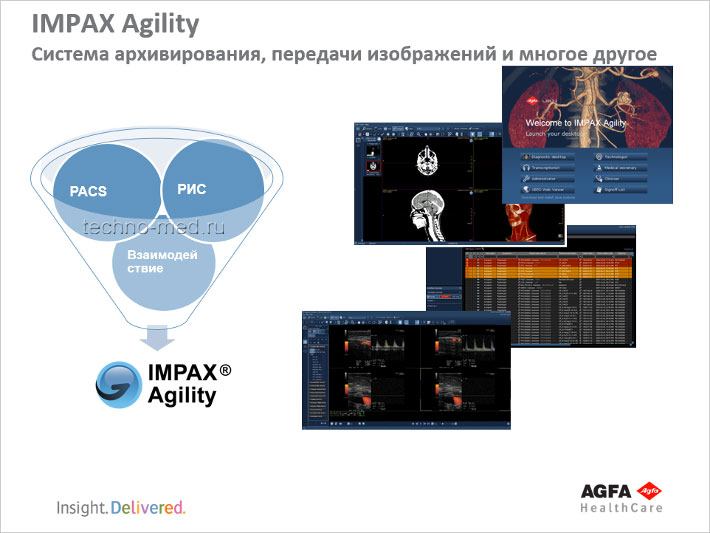

AGFA IMPAX Agility

Система архивирования, передачи изображений и многое другое

AGFA IMPAX Agility - это не просто PACS-машина. Это гораздо больше. Это платформа, которая объединяет в себе многие из программных продуктов. Это не только снижает количество лицензий, но и упрощает работу системы.

IMPAX Agility представляет собой решение для управления медицинскими изображениями, которое